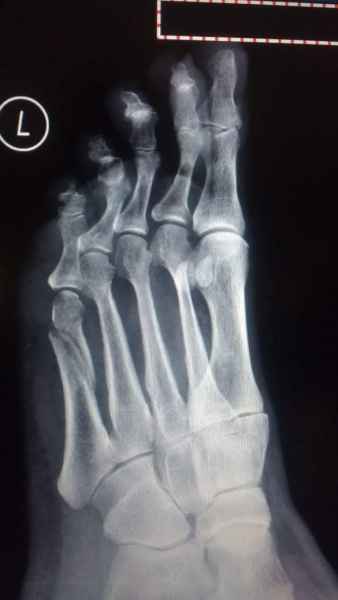

El pie es el órgano distintivo y característico de la especie humana, la única criatura que marcha erguida. El pie es una muy compleja estructura de arquitectura perfecta, adaptado a su función de apoyo, traslación, salto, con una riquísima sensibilidad que le permite detectar las más leves imperfecciones del suelo para estabilizar la marcha.

Tanto la estructura del pie como su funcionalismo que es la marcha, pueden ser asiento y manifestación respectivamente de alteraciones locales ó sistémicas, por lo que su cuidadoso examen resulta de extrema utilidad diagnóstica.